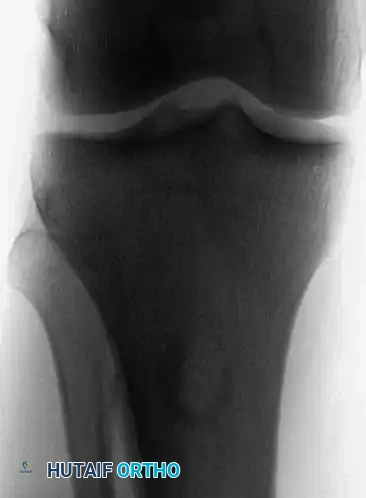

Anteroposterior and lateral radiographs of a 36-year-old man with a 1-year history of right knee pain, demonstrating a chondromyxoid fibroma in its classic location—the proximal tibial metaphysis.